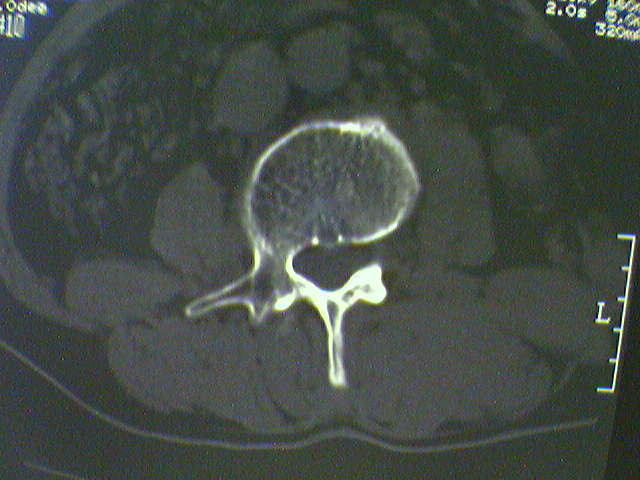

标题: CT15569:男,45岁.腰痛多年,平片腰椎明显侧弯, [打印本页]

标题: CT15569:男,45岁.腰痛多年,平片腰椎明显侧弯,

支持侧弯致退行性骨关节病。

支持腰椎侧弯致退行性骨关节病。